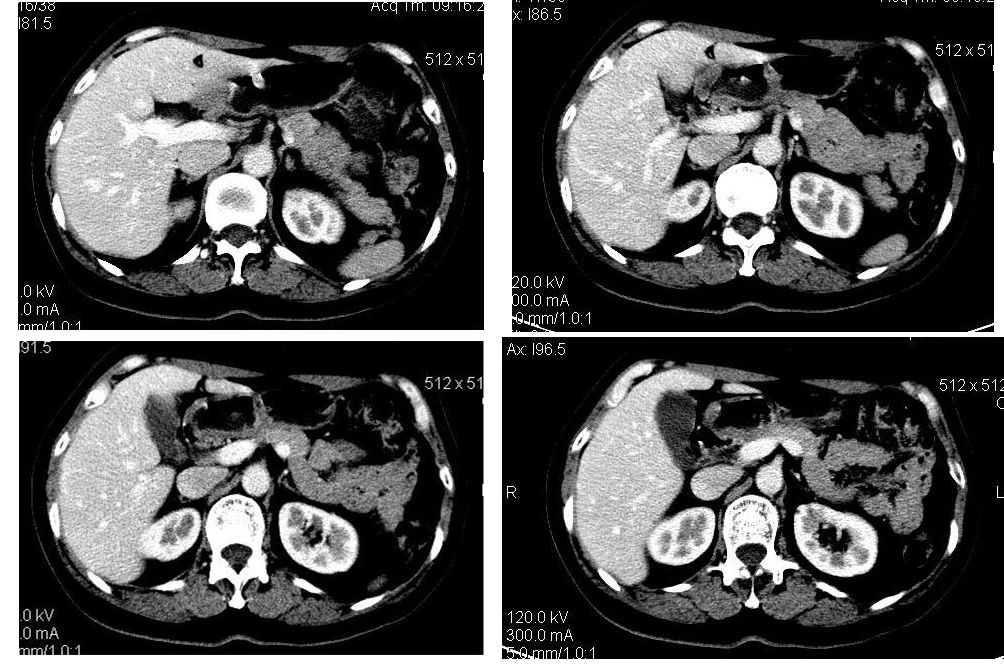

动脉期

门脉期

符合快进快出表现,还是考虑:肝左叶内侧段肝癌.

造影剂快进快出,考虑:肝左叶内侧段肝癌.

肝左叶内侧段低密度灶,增强明显快进快出表现,考虑:肝癌。